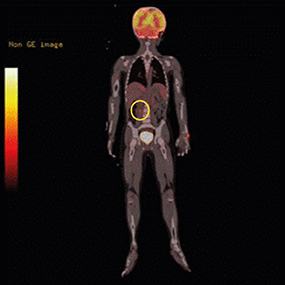

For more detailed examination, magnetic resonance imaging (MRI) was taken. An arterial T1-weighted MRI showed a lobulated mass measuring 3.6×3.8 cm, with high signal intensity, in the right suprarenal area (Fig. 2). Positron emission tomography (PET)-computed tomography (CT) showed hypermetabolism in the right adrenal gland and suggested the need to clarify whether this is a metastatic lesion at the anterior aspect of right psoas muscle (Fig. 3).

Fig. 3

Positron emission tomography-computed tomography. The round circle indicates a hypermetabolic lesion on the right psoas muscle. This lesion was suspicious of metastasis of ganglioneuroblastoma. Multi-disciplinary teams discussed the lesion and concluded that metastasis was not definite.

Abdominal-pelvic CT was performed on July 18, 2019, and it showed a low attenuated, ill-defined mass on the right adrenal gland, indicating a probable neurogenic tumor (Fig. 4). In addition, a metastatic lymph node (LN) along the anterior part of the right psoas muscle appeared suspicious. Multi-disciplinary teams discussed whether the anterior aspect of right the psoas muscle was a true metastatic lesion and made the decision to undergo an operation.